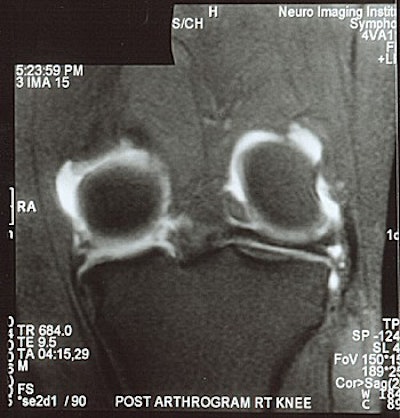

![]() |

| MR arthrogram is needed to demonstrate a meniscal tear in a patient with >25% meniscal resection. |